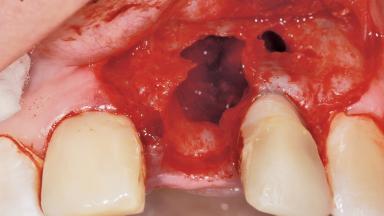

Late Placement of an Implant in a Maxillary Left Central Incisor Site

| Bone Augmentation | Horizontal|Staged |

| Augmentation Materials | Xenogenous|Membrane |

| Bone Volume | Deficient horizontally, requiring prior grafting |

| Soft Tissue Grafting | Simultaneous |